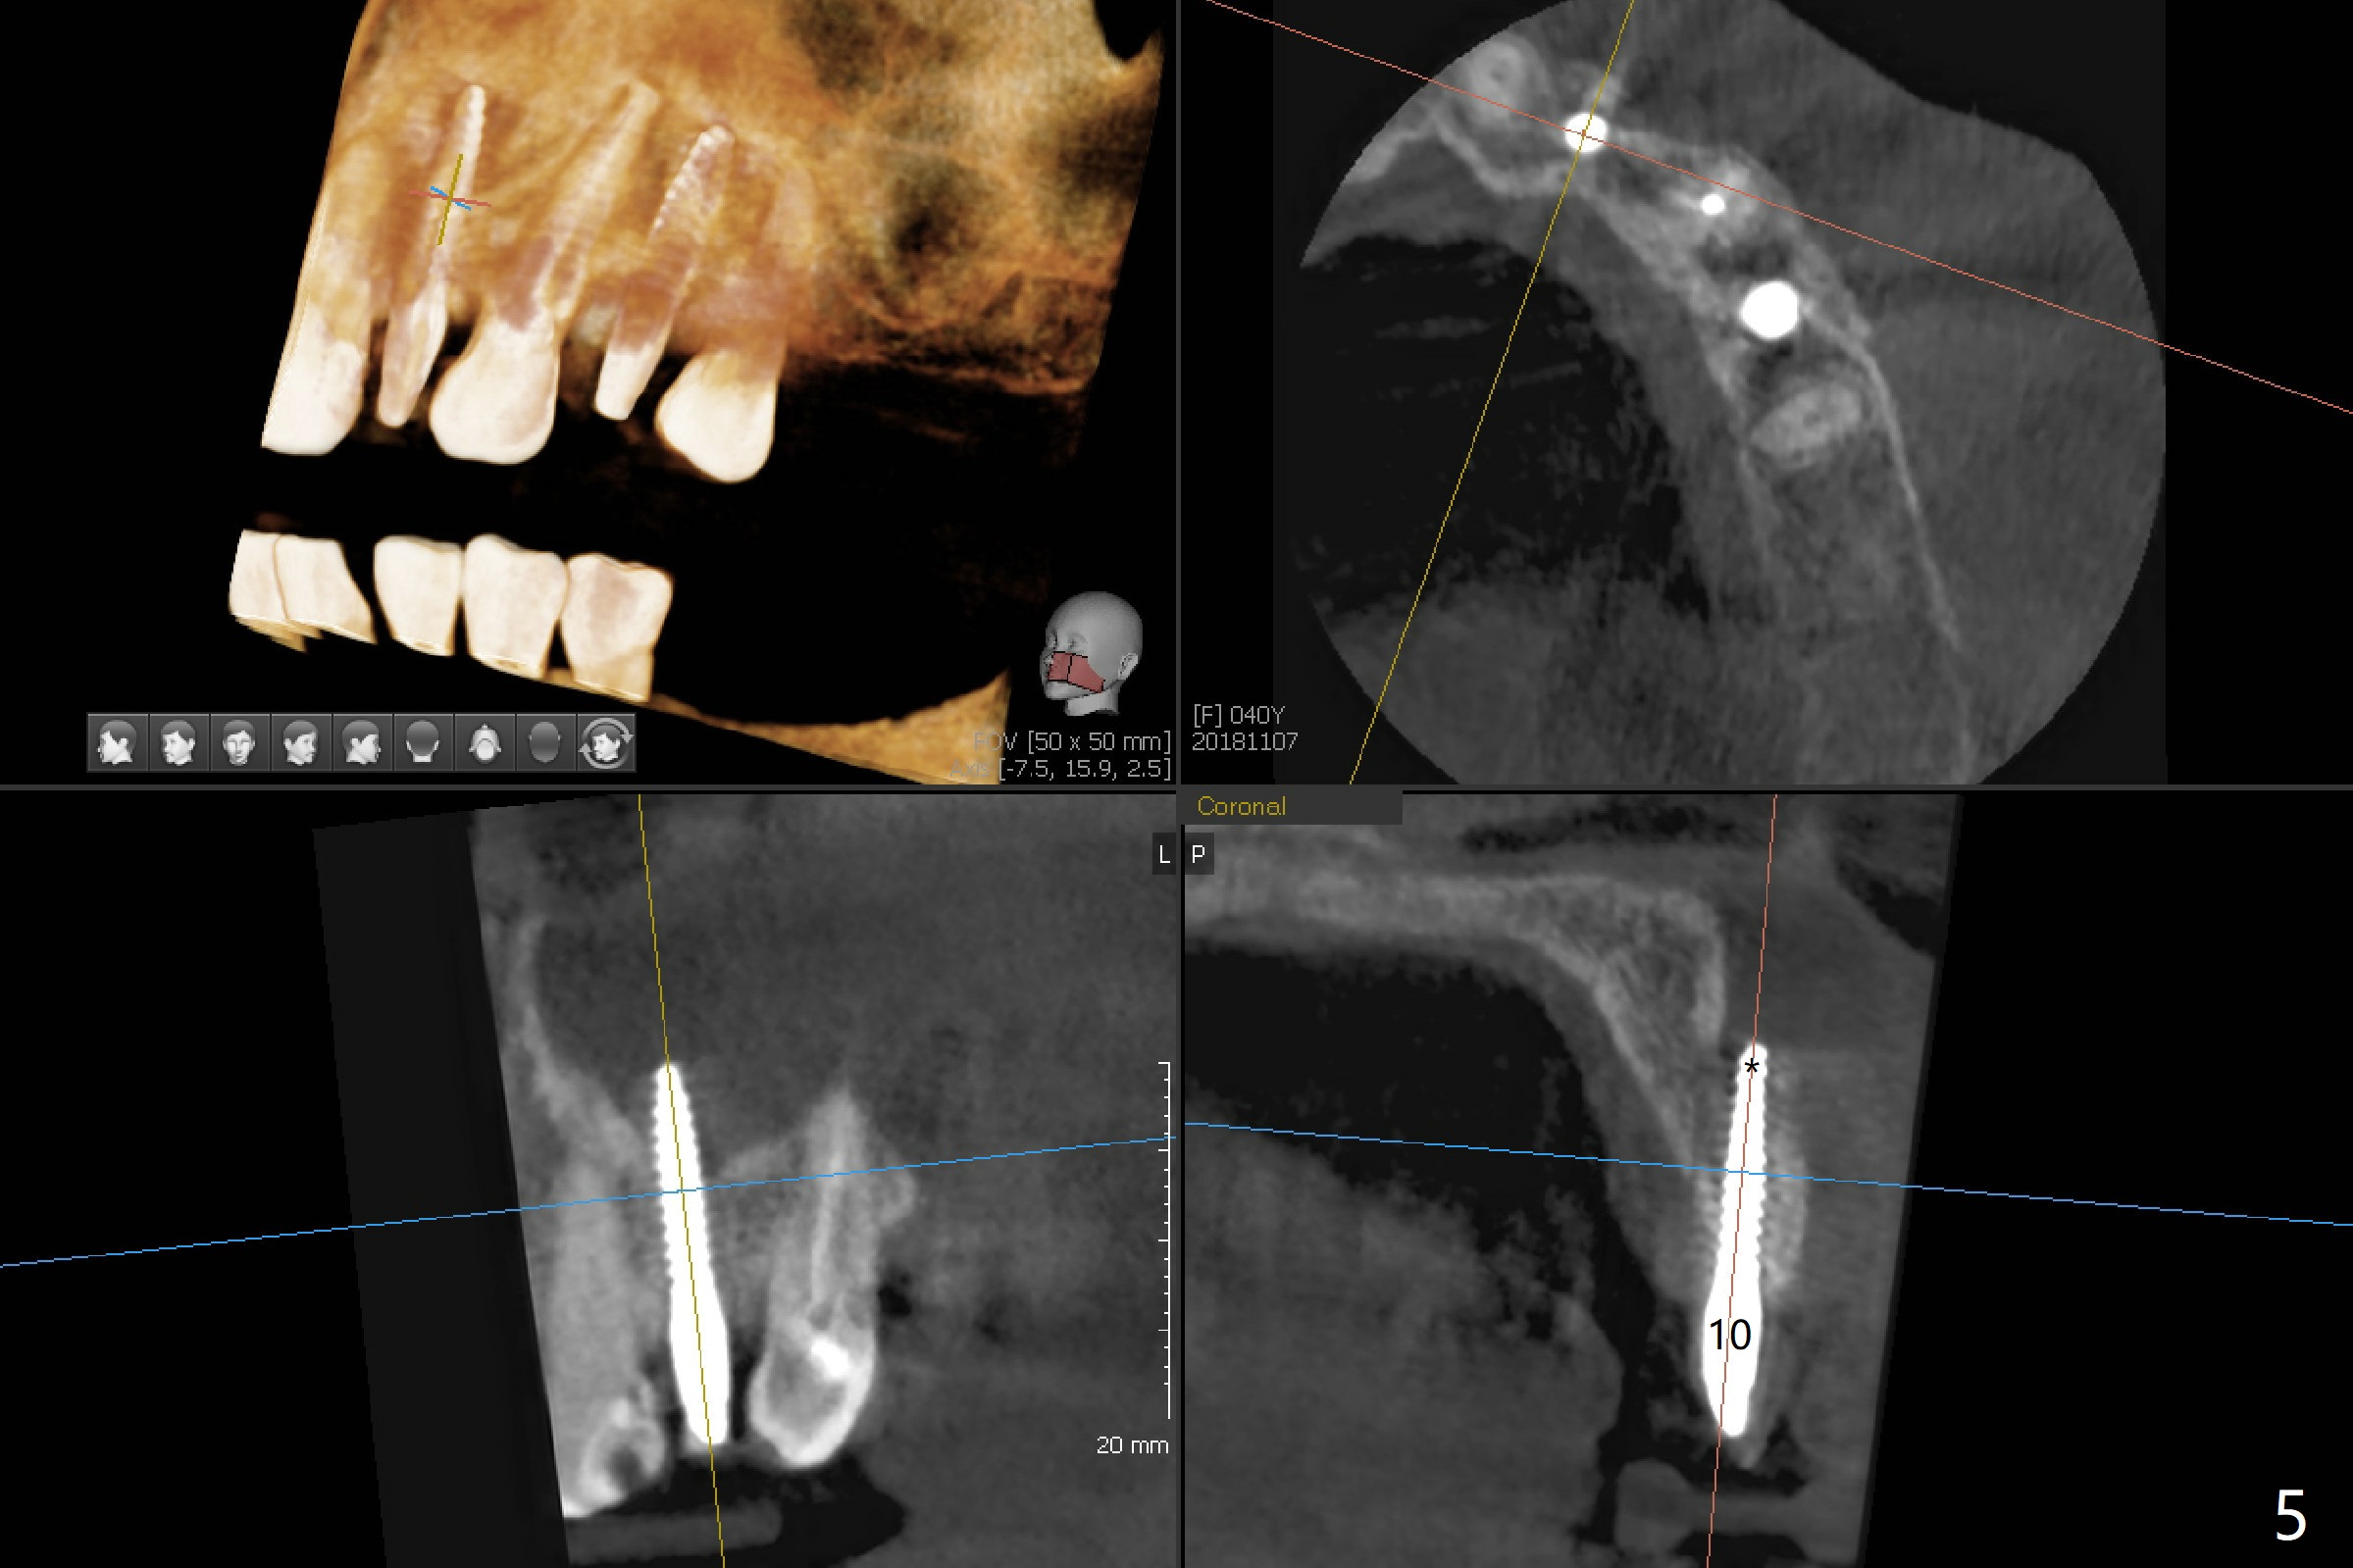

After removal of #10 sleeve and 3 spot adjustment, the guide is seated without satisfaction. When the guide is removed after pointed drill, the osteotomy seems distal (Fig.1). Incision is made with flap elevation for free hand osteotomy. A 1/1.6 mm bone expander is inserted after 1.2 mm drill, the trajectory appears to be right (Fig.2). As the osteotomy increases in diameter, the buccal plate feels to be vibratory. A 3.5x11.5 mm 1-piece implant placed initially is apparently away the sinus floor (Fig.3). Further placement (subcrestal, Fig.4) seems to be associated with more buccal plate perforation (Fig.6 *), which is repaired by bone graft. Since the implant at #10 appears to be doing okay 1.5 months postop (Fig.5), the implant at #12 is not removed immediately. A tunnel incision will be made for bone graft in the most apical concave areas (Fig.7). The osteotomy should have been made more palatal to reduce the chance of the buccal perforation. CBCT should have been taken while the 1/1.6 bone expander was in place.